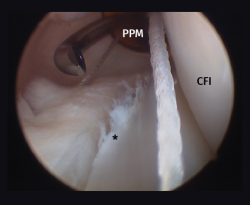

Although recently greater importance is being placed on the presence of so-called meniscal ramp lesions (Figure 3), with an estimated incidence of up to 23.9%(19) associated to ACL rupture, these lesions were already described by Strobel(20) in 1988 as a particular type of meniscal injury associated to ACL rupture and affecting the peripheral insertion of the posterior horn of the medial meniscus. These injuries are also referred to as hidden lesions of the posterior horn of the medial meniscus, since they may go undetected in the MRI studies(21). From the biomechanical perspective, ramp lesions of the knee with ACL rupture increase anterior translation of the tibia, internal and external rotation, and pivot shift. If not repaired, rotational stability following reconstruction of the ligament likewise is not fully restored(22).

Figure 3. Repair of a lesion of the posterior ramp of the medial meniscus (*) adopting a posteromedial arthroscopic approach. Trans-notch view from the anterolateral port. Working cannula in the posteromedial port (PMP). IFC: internal femoral condyle. Right knee.